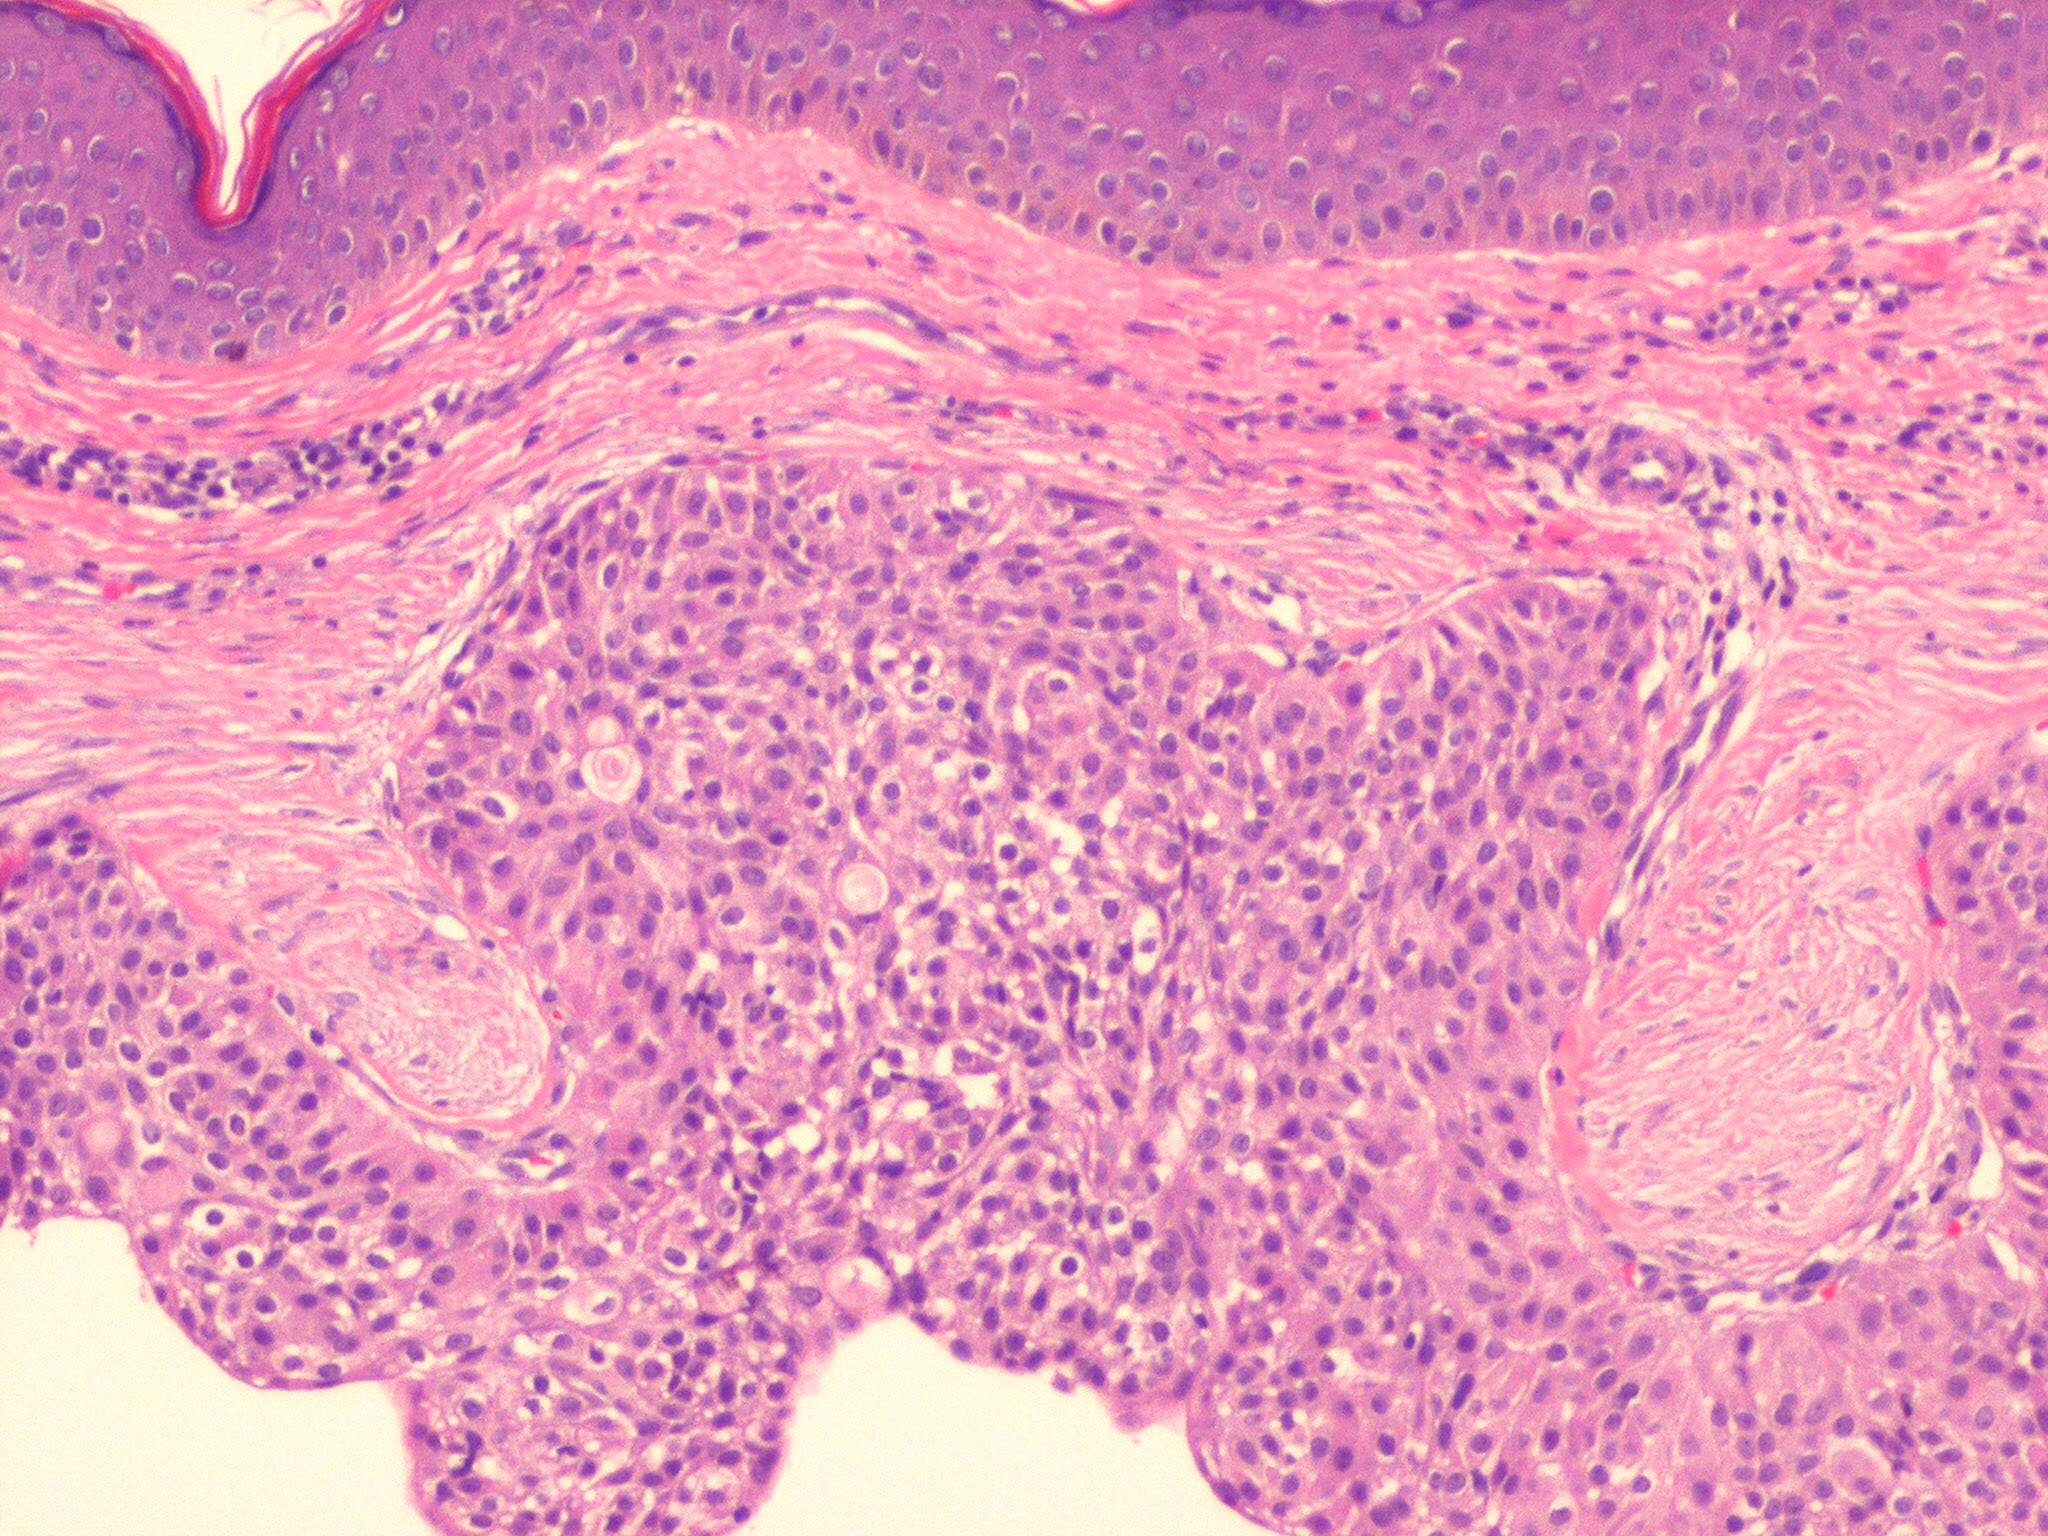

A nodular, solid, or solid-cystic lesion in the dermis, sometimes with extension to the subcutis . The epithelial component consists of closely packed aggregations of round, fusiform, or polygonal cells with either eosinophilic or clear cytoplasm. Individual lesions show a variable cellular composition. Clear cells predominate in about one-third of cases. Mitotic figures are sometimes noted within the epithelial component, a feature that does not generally indicate malignancy. The cystic spaces are often filled with mucin.